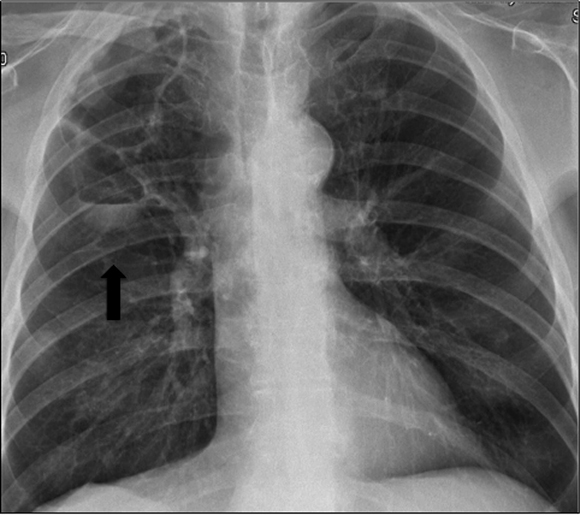

Three months after restarting Sorafenib treatment, he again had asthenia, cough and purulent sputum. A chest X-ray showed an enlarged pneumatocele (Figure 4). Empiric antibiotic therapy with clindamicyn and voriconazol was prescribed. Aspergillus fumigatus was again isolated in the sputum but not in the BAL culture. Symptoms improved although the size of the cavity remained stable. Sorafenib was permanently discontinued after 14 months, recessed and the patient died one month later because of tumor progression.

Figure 4: Pneumatocele enlargement detected in chest X-ray (black arrow) (Case 2).